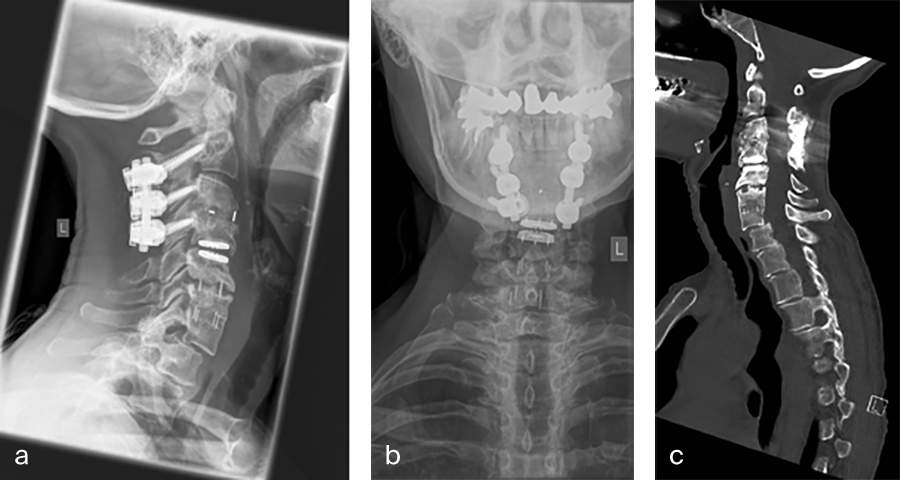

Her preoperative radiographic evaluation comprised x-rays, functional x-rays, computed tomographic, and magnetic resonance imaging scans (Fig 4) and demonstrated:

- A fusion of the motion segments C2/3/4 and C6/7

- A moderate implant loosening of the posterior C2 screw on the right side

- An afunctional disc prosthesis at the level C4/C5 with significant heterotopic ossifications (grade III) accompanied by a facet joint osteoarthritis in this motion segment

- A nonunion at the level C5/C6 with residual mobility in this motion segment

- A highly mobile degenerative spondylolisthesis at the level C7/Th1 with bilateral neuroforaminal stenosis

Preoperative imaging (Fig 4a-f), showing:

- C2-C4 posterior instrumentation and fusion.

- Anterior fusion after Anterior Cervical Decompression and Fusion (ACDF) C3/4 and C6/7.

- Status after total disc replacement of C4/5 with heterotopic ossifications.

- Nonunion C5/6 after ACDF C5/6.

- Spondylolisthesis C7/Th1 with neuroforaminal stenosis on both sides.

-  A normal cervical angiogram (cave: artefacts).